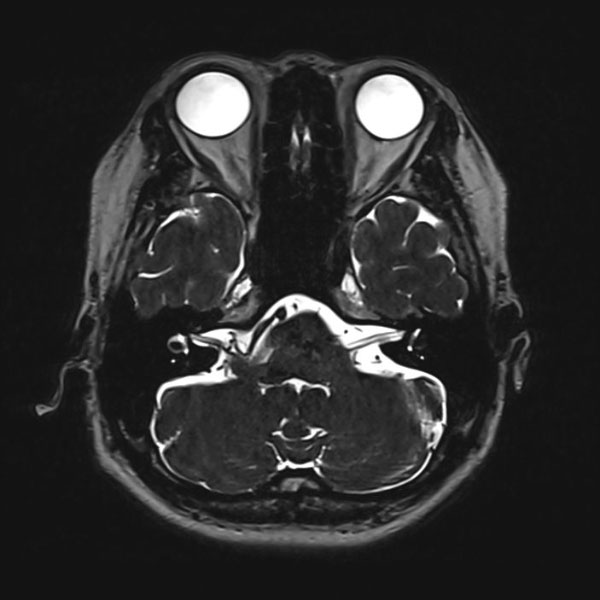

右顔面痙攣